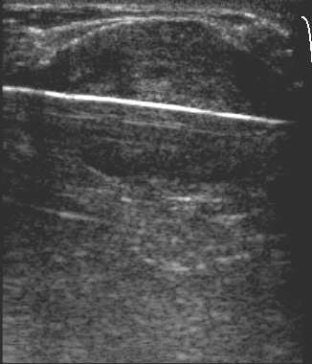

| Ultrasound images during cryoablation showing an ice-ball formation with a cryoprobe through the center of fibroadenoma. Above, longitudinal axis; below, transverse axis. Images courtesy of Dr. Dennis R. Holmes, breast surgeon and director of new technology development, University of Southern California/Norris Comprehensive Cancer Center and Hospital, and chief, breast service, LAC+USC Medical Center, Los Angeles. |

Ultrasound-based breast procedures improve accuracy and efficiency, expand treatment options, and expand billable services "at a time of rising practice expenses and declining reimbursements," said Dr. Dennis Holms, director of new technology development and a breast surgeon at the USC center.